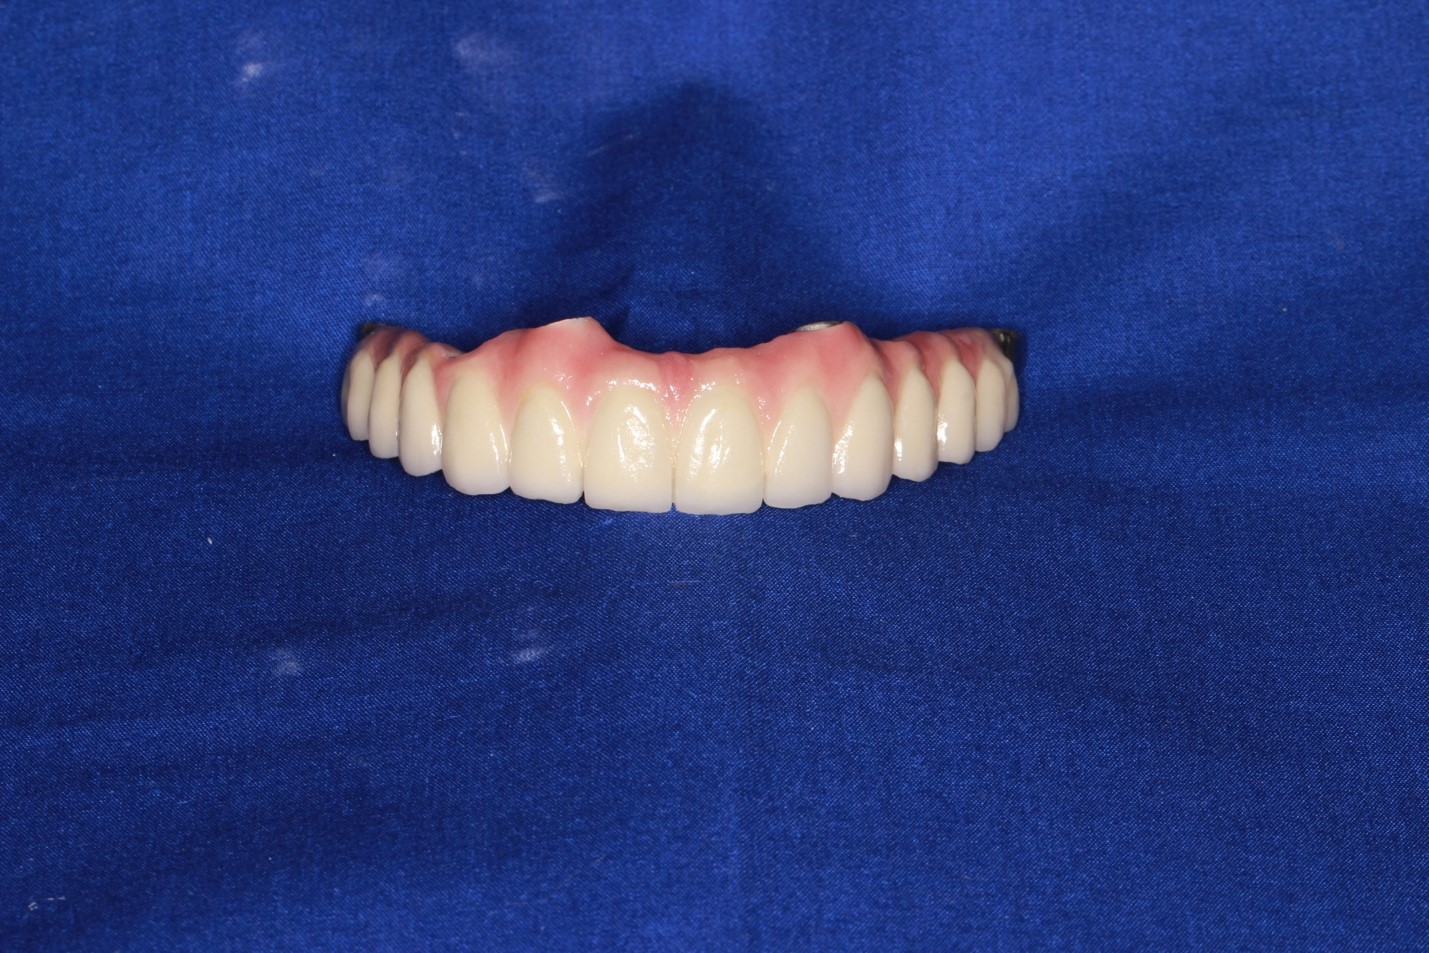

Далее импланты интегрировались и мы стали делать постоянный протез:

Далее поверх этого металла мы нарастили керамику, стало вот так:

Это контроль промывных пространств, окончательные протезы, окончательный внешний вид

На этой стадии пациент мог весело улыбаться, открывать пиво зубами (не рекомендуется, но технически мог бы), жевать стейк любой прожарки без усилий и в экстренных ситуациях перекусывать во рту металлический кабель сечением до 12 мм без особых последствий (строго не рекомендуется, даже на спор). Металлы основания конструкции — кобальт и хром. Обычно альтернатива металлокерамике — титановый каркас и цирконий, но в данной ситуации из-за геометрии такой сборки возможности её использовать почти не было, и выбрали керамику на кобальт-хроме. К титану керамика не крепится, не удерживается. Десна, естественно, не могла быть восстановлена, поэтому она фактически нарисована на керамике — это так называемая высокоэстетичная конструкция, то есть при разговоре можно и не догадаться, что зубы ненатуральные (если вы не врач).